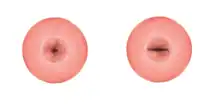

The ectocervix (also known as the vaginal portion of the cervix) has a convex, elliptical shape and projects into the cervix between the anterior and posterior vaginal fornices. On the rounded part of the ectocervix is a small, depressed external opening, connecting the cervix with the vagina. The size and shape of the ectocervix and the external opening (external os) can vary according to age, hormonal state, and whether childbirth has taken place. In women who have not had a vaginal delivery, the external opening is small and circular, and in women who have had a vaginal delivery, it is slit-like.[8] On average, the ectocervix is 3 cm (1.2 in) long and 2.5 cm (1 in) wide.[3]